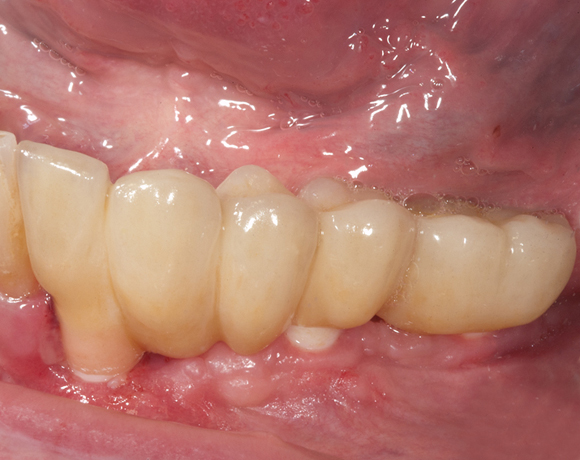

Knochenspaltung Unterkiefer 32 – 36

Bei diesem Patientenfall war vor dreizehn Jahren bereits eine Knochenspaltung besprochen

worden, die Patientin hatte allerdings Angst vor dem Eingriff und sich für eine herausnehmbare

Lösung entschieden. Nachdem die endodontisch behandelten Zähne 32 und 33, die mit VMK – Kronen

und Geschiebe versorgt waren, abgebrochen sind, war die Patientin für den Eingriff mit Knochen-

spaltung und drei Implantaten offen. Heute ist sie sehr zufrieden und bereut es nicht gleich diese

Lösung gewählt zu haben.